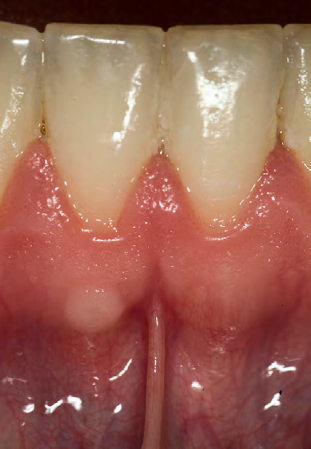

What is this clinical finding?

A parulis

It is not a pyogenic granuloma

A parulis is a proliferation of granulation tissue at the opening of a sinus tract

When the infection breaks through the alveolar bone and presents itself,

it will sometimes cause this proliferation of granulation tissue